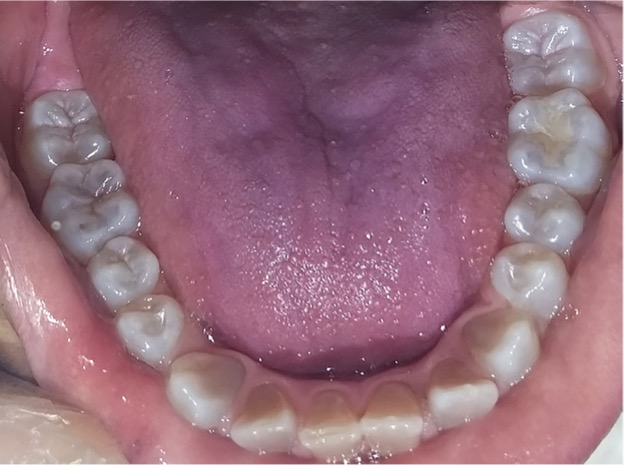

En la radiografía panorámica de control del año 2015 se observó la progresiva obliteración del conducto radicular en el grupo incisivo superior e inferior y en los primeros molares permanentes; presentado los premolares en erupción, un conducto radicular anormalmente amplio en toda su longitud (Figura 8). En la del año 2018 se visualizó la continua aposición de dentina a nivel radicular que obliteró en forma casi total los conductos de la mayoría de las piezas dentarias, a excepción de los segundos molares inferiores (Figura 10).

Figura 10: Rx panorámica 2018.

Debido el alto porcentaje de abscesos periapicales, producto de la obliteración progresiva de los conductos radiculares, es fundamental el monitoreo radiográfico periódico en pacientes con DI.1 Los controles con radiografías panorámicas fueron realizados en el 2007, 2010, 2015 y 2018, sin registro de patologías pulpares periapicales.